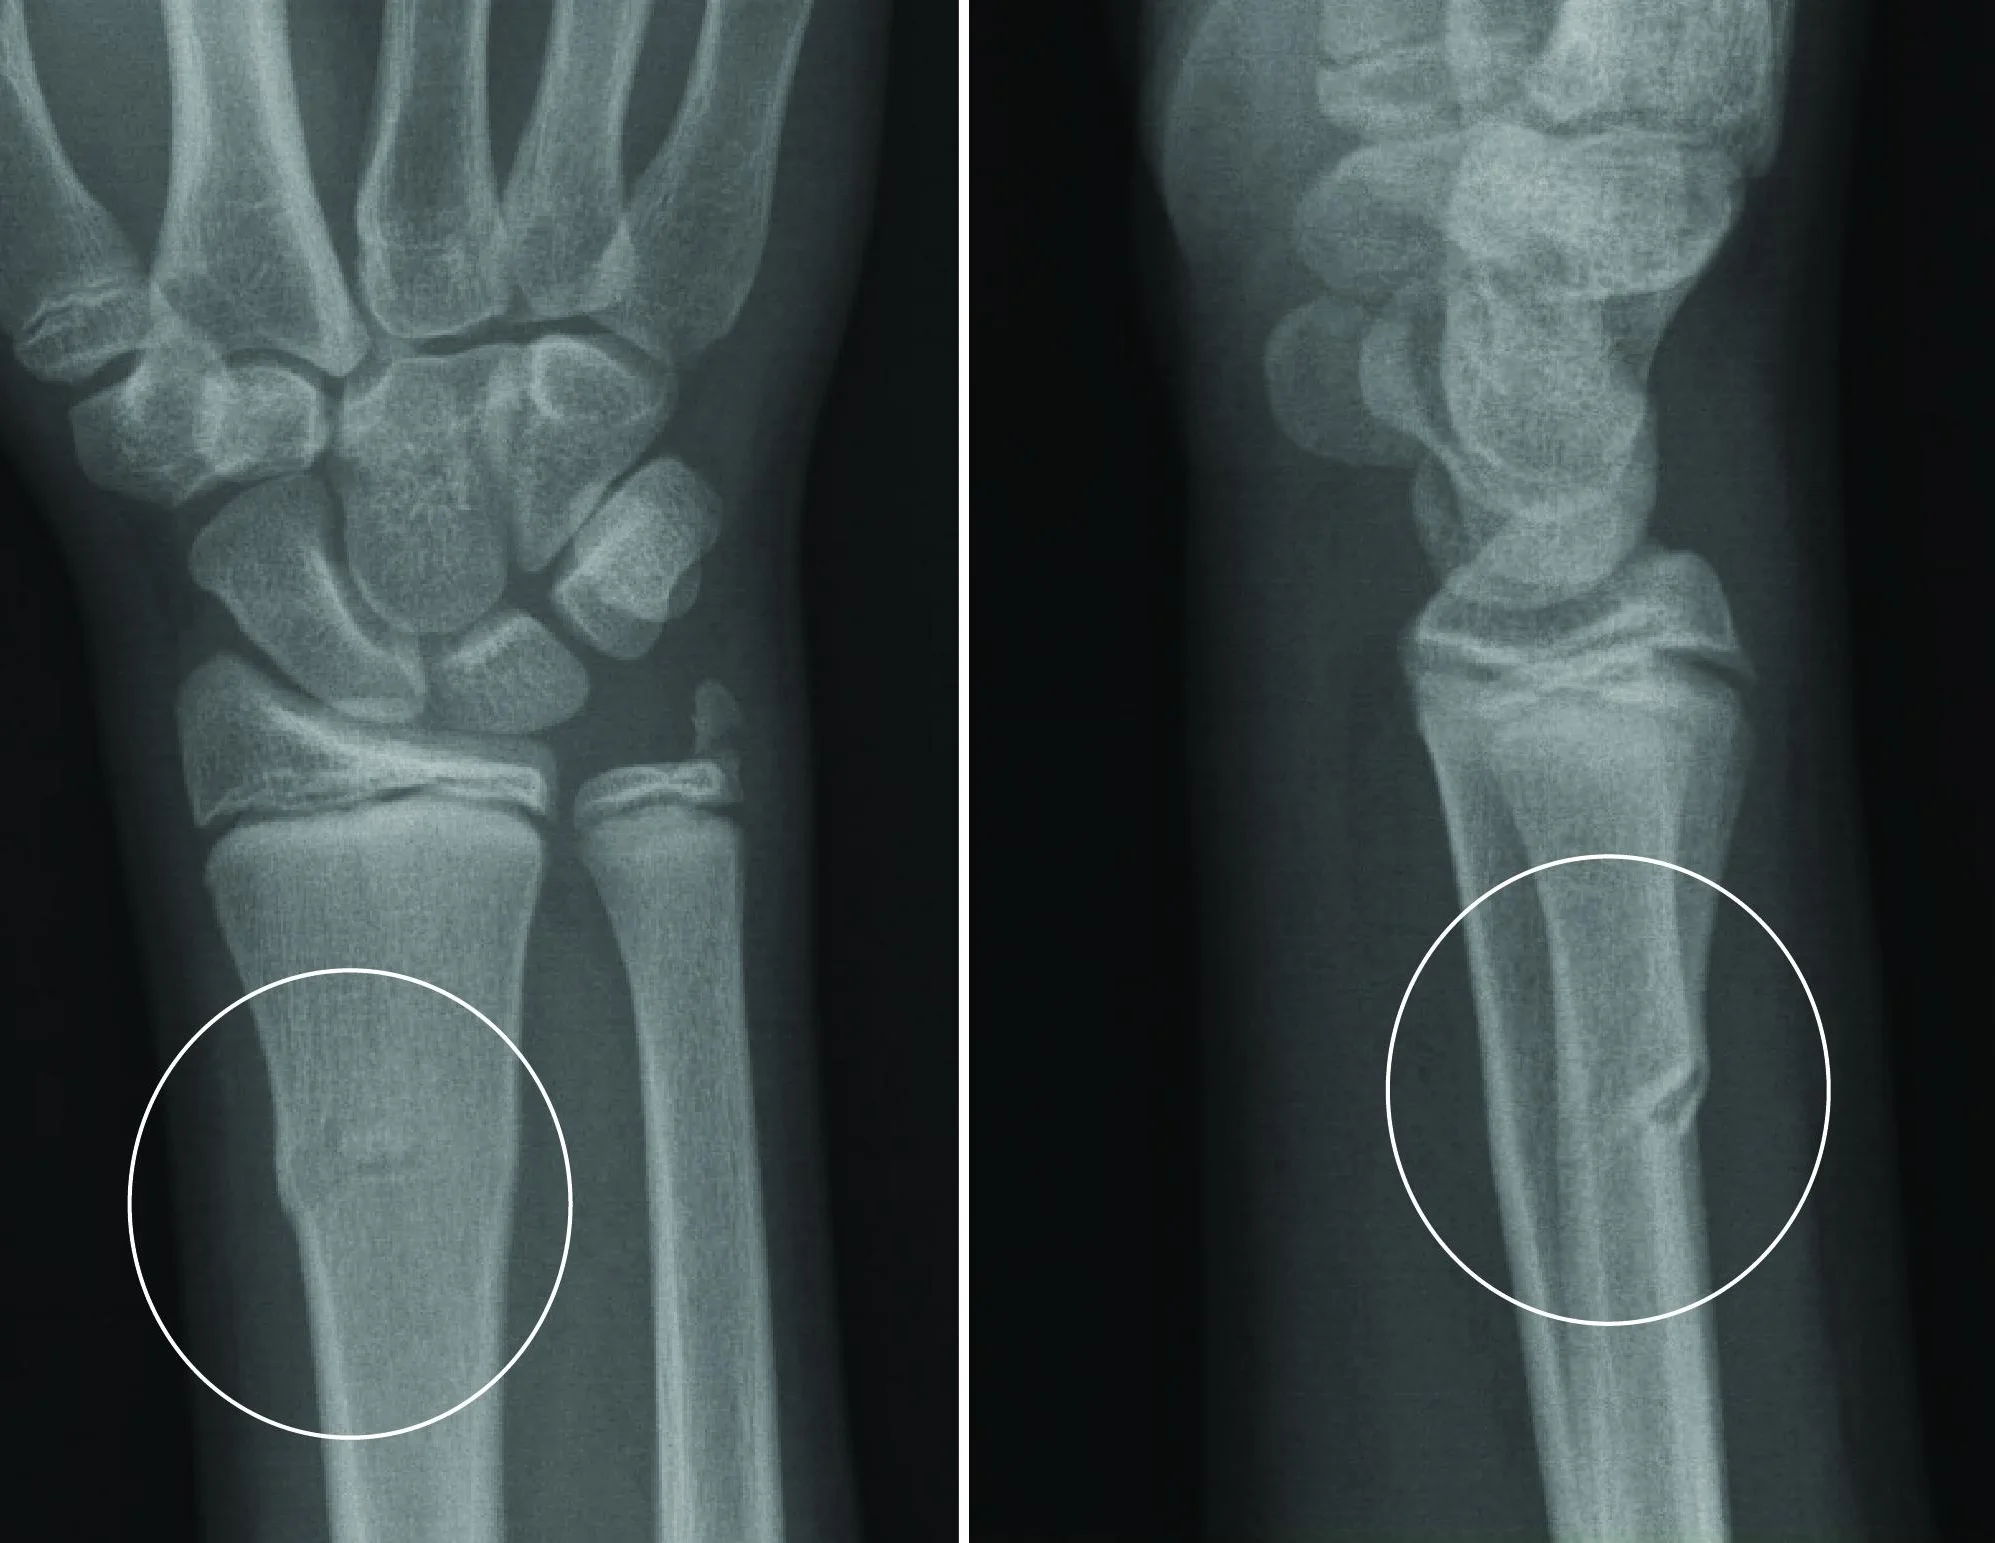

Изображения повреждения костей